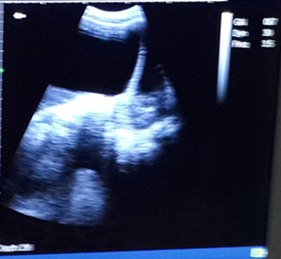

Radiological investigation: Ultrasound was done and revealed a large partitioned anechoic image near the lower pole, centered in a slightly echogenic area, posterior reinforcement (Additional file 1). The size of the image were not easily taken due to the extension of the tumor beyond the monitor screen. . The uterus had no abnormality. The right ovary was visualized and was normal without abnormality. The liver, spleen and renal ultra-sound scans were unremarkable. Intestinal loops pushed back towards the sides, not surrounded by liquid. The abdominopelvic ultrasound concluded that those features were consistent of a giant cyst in favor of the left ovary.

Additional file 1 Trans-abdominal ultrasound image showing a giant left ovary cyst with cumulus oophorus.